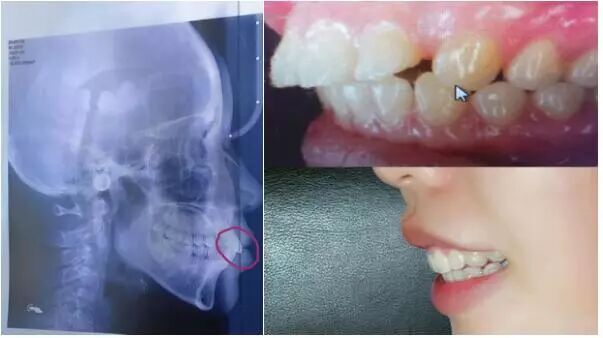

牙不齐、对牙不满的苦恼

牙齿矫正